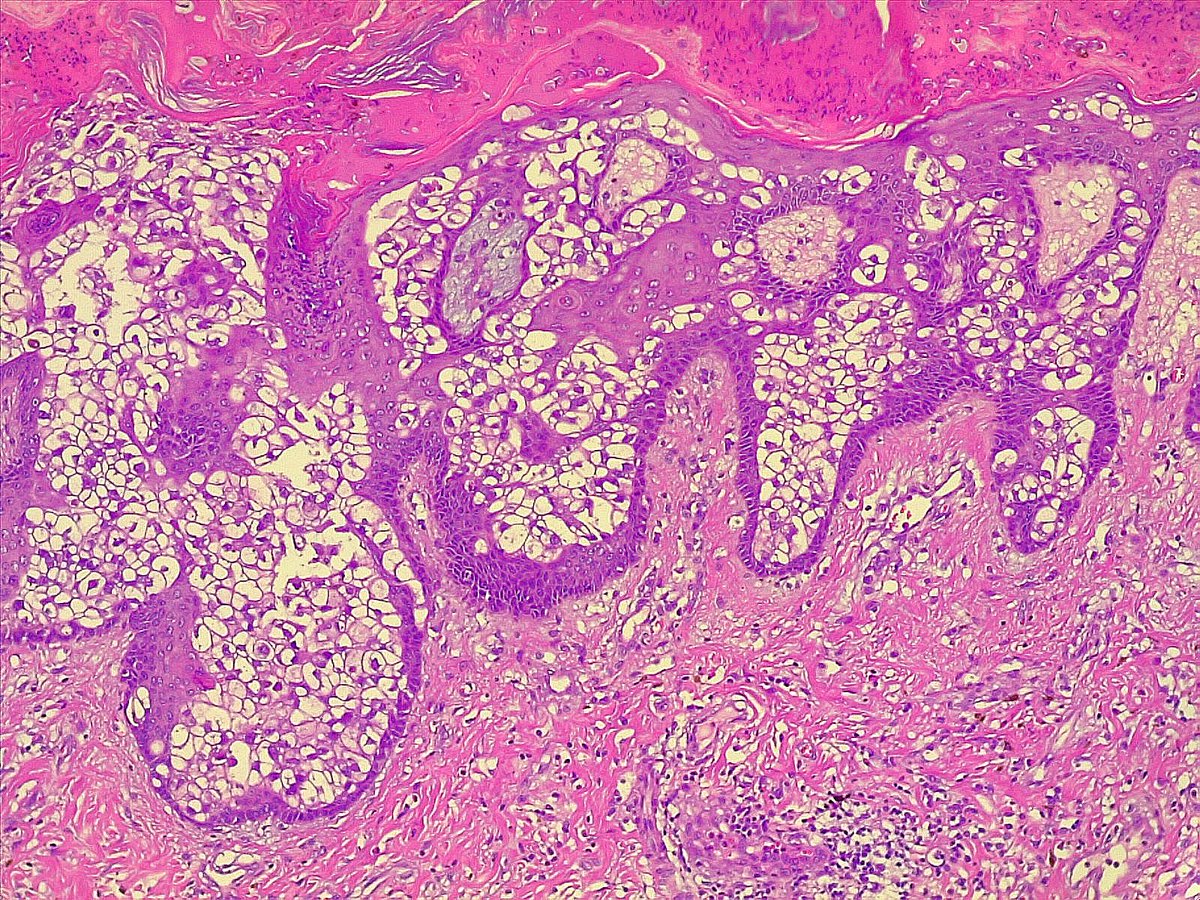

Clear cell Paget disease of nipple with high grade DCIS showing clear cell changes, couldn't resist sharing it with you #PathX #PathTwitter

Case of Apocrine Ductal Carcinoma in Situ (DCIS) 🌸🔬 Apocrine DCIS displays hallmarks of apocrine differentiation with marked cytologic atypia and central necrosis. Some have suggested a size threshold of 4 mm extent for the diagnosis. #PathX #PathTwitter #breastpath